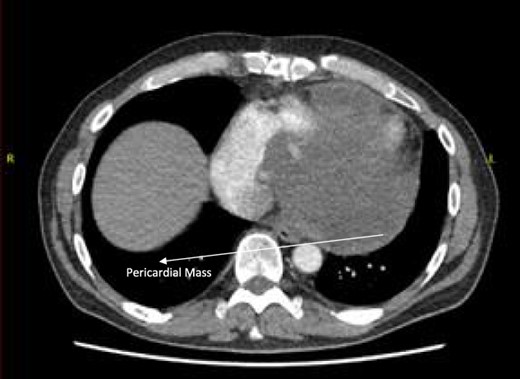

Follow-up CT scans were undertaken during chemotherapy that showed continued reduction in the size of the RA tumour, as demonstrated in Figs 4 and 5. The pericardial mass following chemotherapy is visualized in Fig. 6.

Post-operative CT scan showing pericardial mass following chemotherapy.